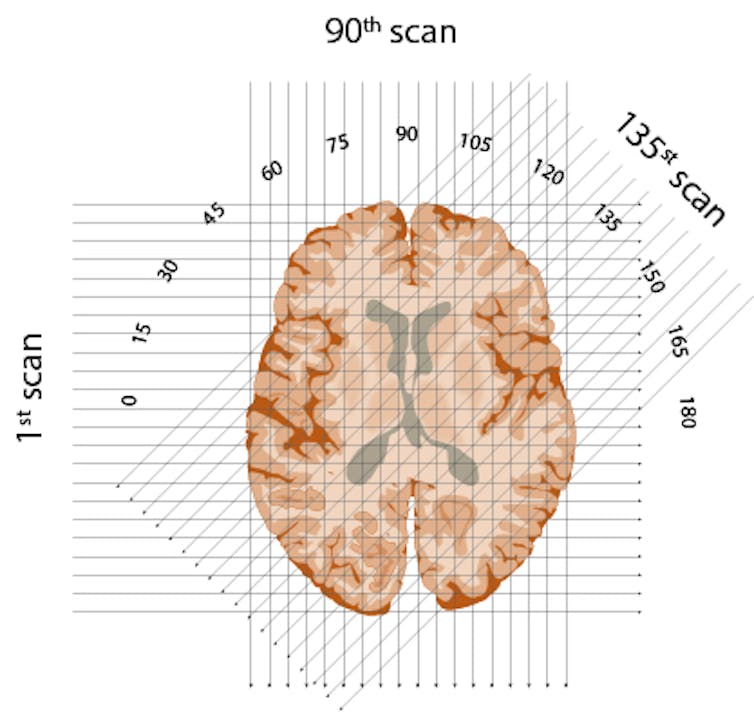

First, he would conceptually divide the brain into consecutive slices – like a loaf of bread. Then he planned to beam a series of X-rays through each layer, repeating this for each degree of a half-circle. The strength of each beam would be captured on the opposite side of the brain – with stronger beams indicating they’d traveled through less dense material.

Finally, in possibly his most ingenious invention, Hounsfield created an algorithm to reconstruct an image of the brain based on all these layers. By working backward and using one of the era’s fastest new computers, he could calculate the value for each little box of each brain layer. Eureka!